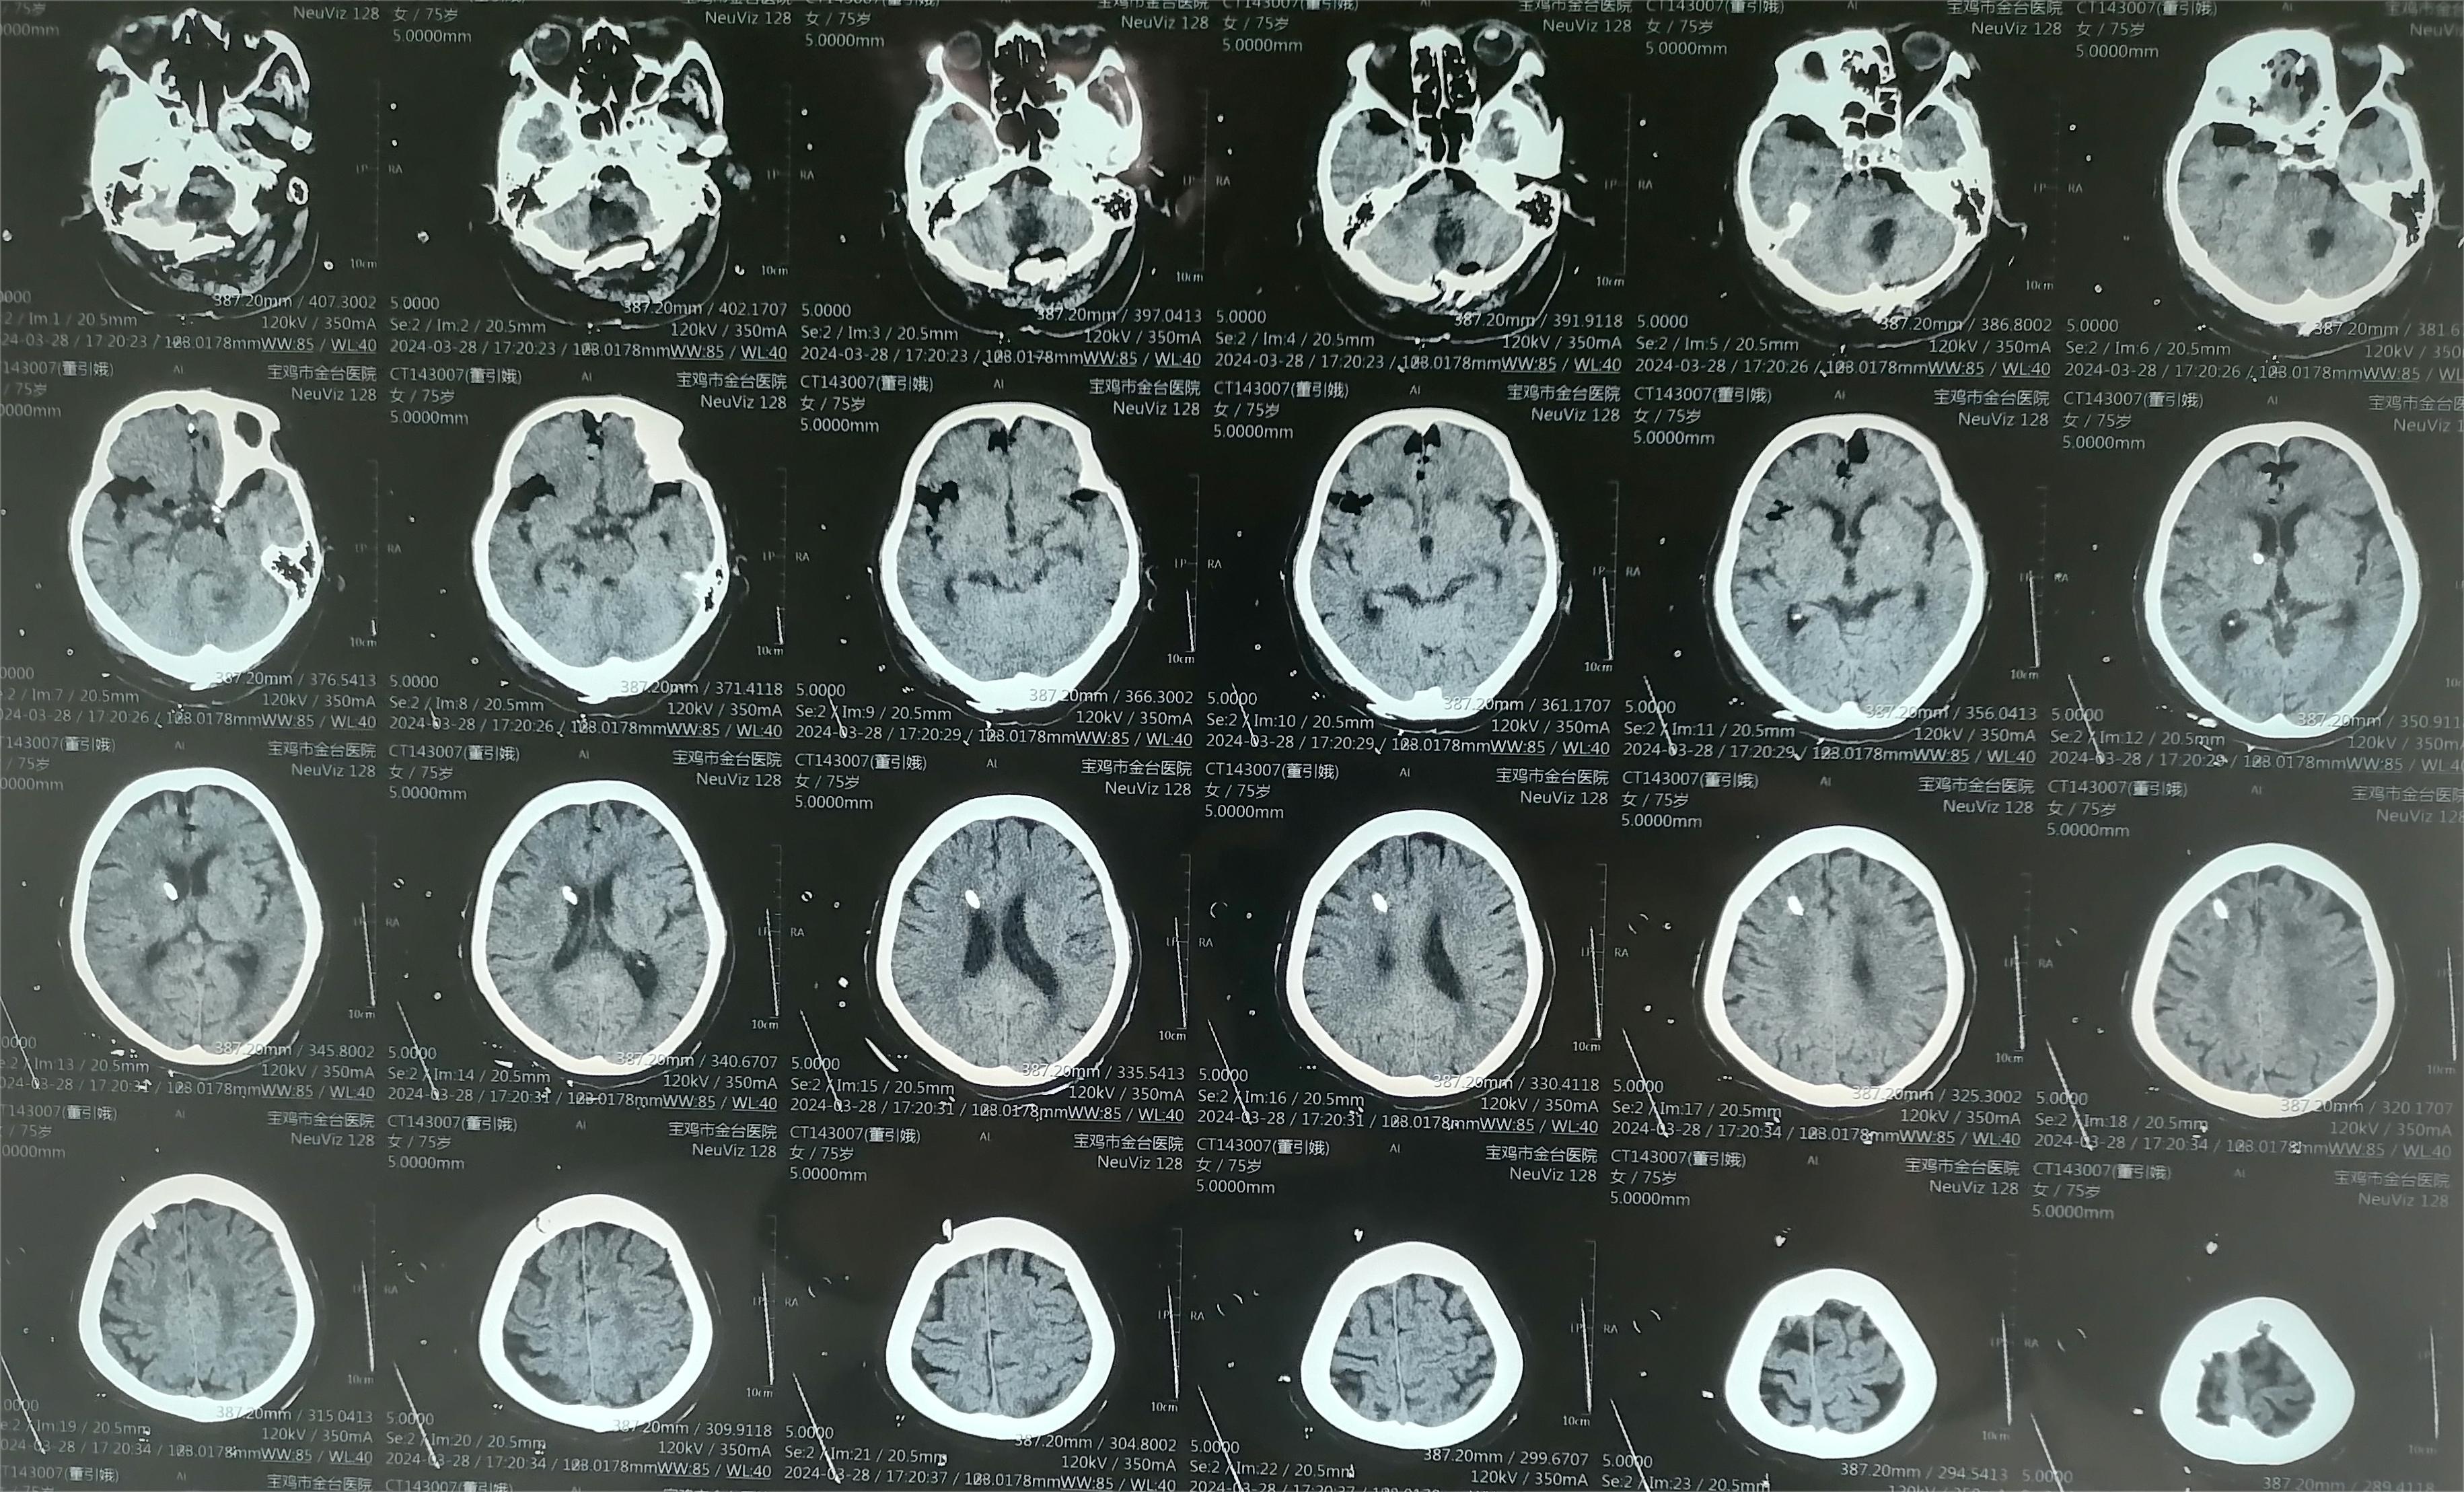

术前资料

术后资料